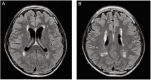

Human coronavirus OC43 (HCoV-OC43) is predominantly associated with mild respiratory infections. HCoV-OC43 also has neuroinvasive properties, and severe encephalitis has been described in immunocompromised patients, with fatal outcomes due to the lack of specific antiviral treatment. We report a case of severe febrile encephalitis attributed to HCoV-OC43 that progressively worsened over 3 months in a 65-year-old immunocompromised man. Clinical symptoms improved remarkably after treatment with remdesivir, with an increase of the Glasgow Coma Score from 8 to 14 within 7 days.